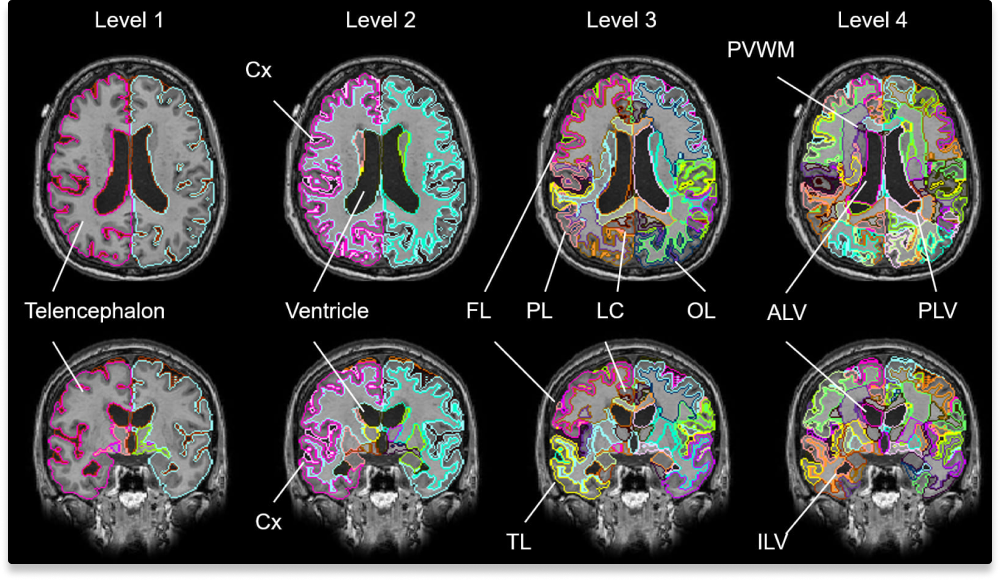

AIが認知症リスク因子を定量化

認知機能低下の要因となる脳萎縮や白質病変、全脳505構造を解析。人間の目では評価が難しい微細な変化も定量化します。